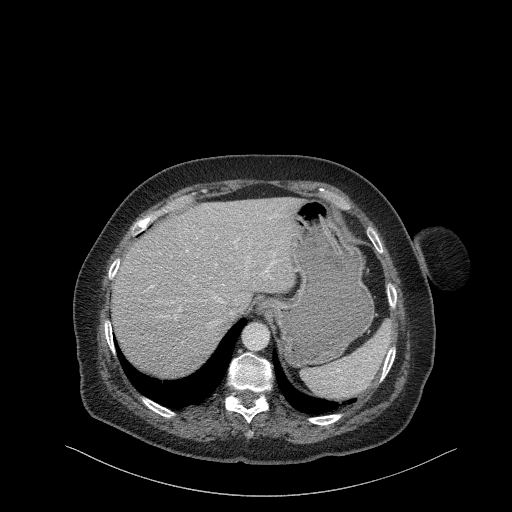

Original VENOUS CT scan

Full window (WL 1023.5, WW 4095 β†’ Low βˆ’1024, High +3071)

Actual HU range: [-160.0, 240.0]

Lung window (WL -600, WW 1500 β†’ Low βˆ’1350, High +150)

Actual HU range: [-160.0, 150.0]